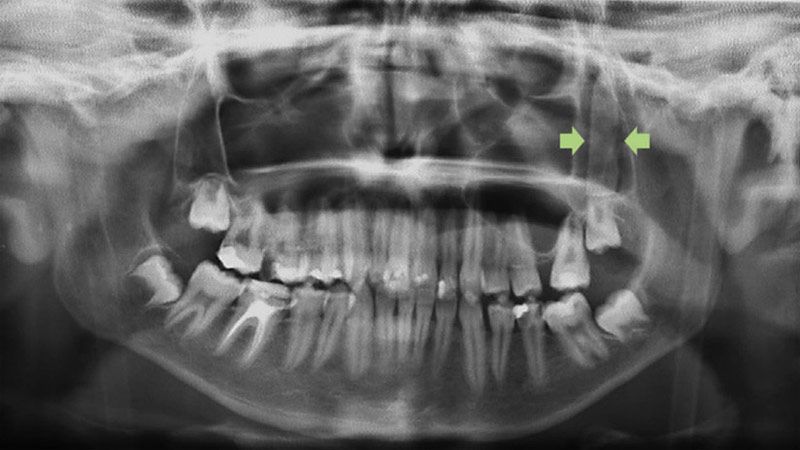

En el Hospital Universitario Virgen del Rocío le hicieron una radiografía y una tomografía computarizada que reveló la existencia detrás de un pómulo de un objeto rectangular de unos 3,5 centímetros de longitud "que tenía forma de hoja de cuchillo".